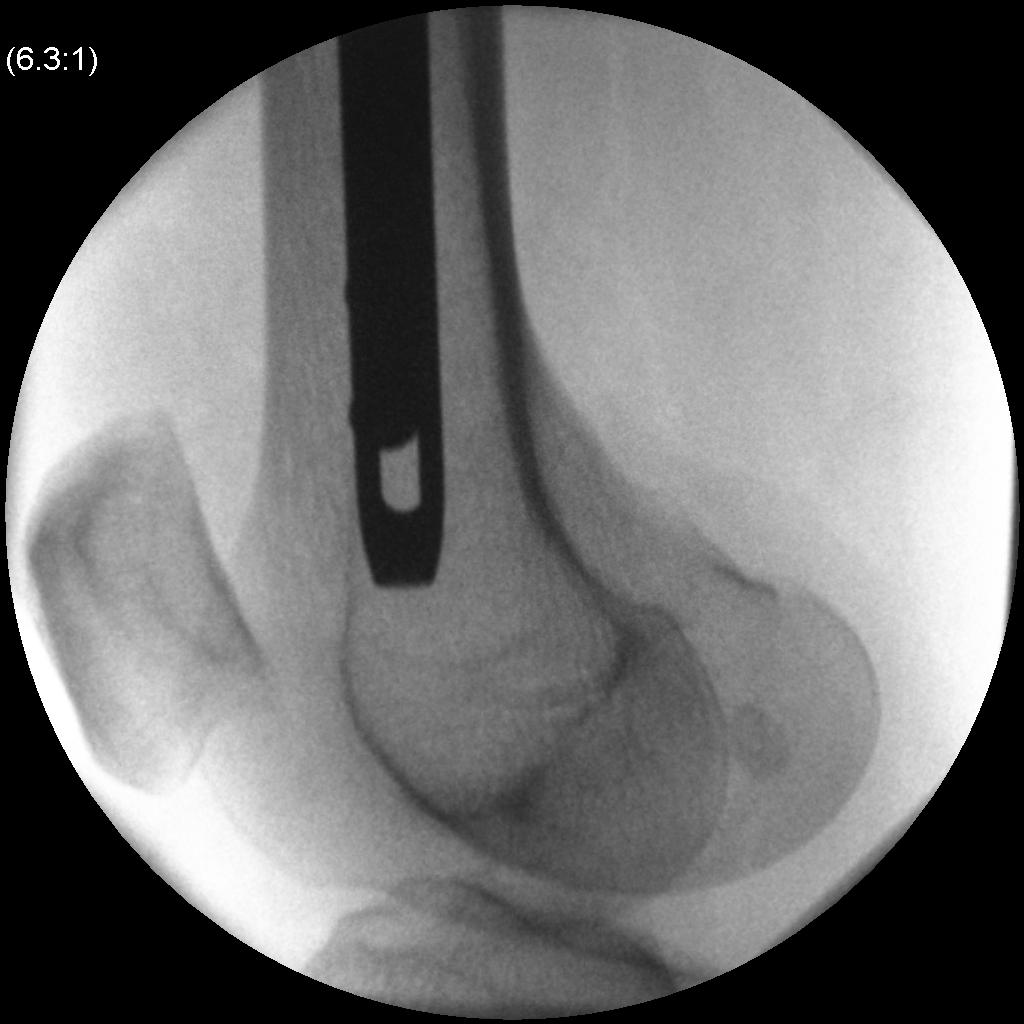

Entry

- incision proximal to GT

- split abductors in line

- palpate tip of GT

- check entry point on AP xray view

- check entry point on lateral xray view (junction anterior 1/3 posterior 2/3)

- entry with awl or 3.2 mm guide wire

- ensure wire doesn't penetrate medial cortex

- use proximal reamer for thickened proximal portion of nail

Pass guide wire

- ball tipped

- femoral fractures difficult to reduce with traction

- use reduction tool to reduce in AP and lateral views to pass guidewire

- if having difficulty +++, can perform miniopen incision to pass guide wire

- measure guide wire to determine nail length

Note typical deformity of proximal fragment which needs to be corrected

- flexed by psoas

- abducted by G medius

- externally rotated